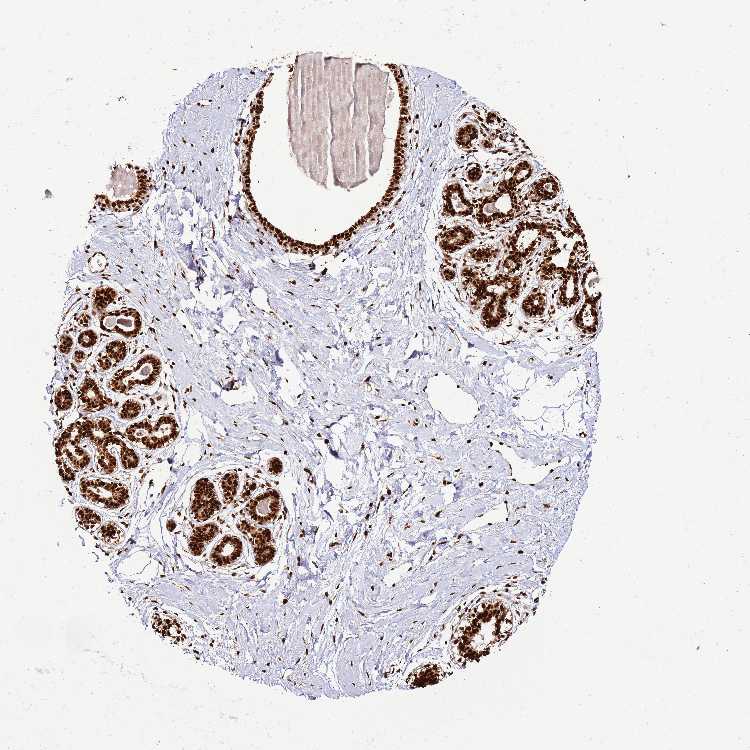

TISSUE PRIMARY DATA BREAST Show tissue menu

BREAST - Antibody stainingi

Antibody staining in the annotated cell types in the current human tissue is reported as not detected, low, medium, or high, based on conventional immunohistochemistry profiling in selected tissues. This score is based on the combination of the staining intensity and fraction of stained cells.

Each image is clickable and will lead to virtual microscopy that enables deeper exploration of all samples and also displays staining intensity scores, fraction scores and subcellular localization as well as patient and tissue information for each sample.

Antibody HPA046688

Adipocytes High

Glandular cells High

Myoepithelial cells High